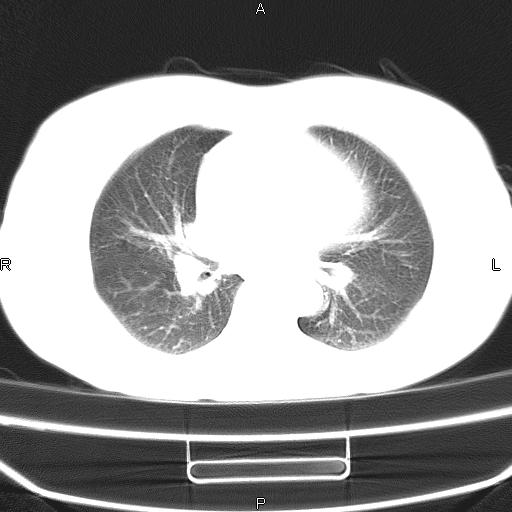

患者,女,66岁。健康体检胸部透视发现右上肺片状阴影。既往无不适,患者自诉三个月前曾有低热病史体温37.5左右一周。用药后缓解。至今无其它不适。请老师们指导指导。

考虑:右肺上叶周围型肺癌(分叶状肿块+砂粒状钙化+胸膜尾征)。

病灶见明显分叶、大小较大(大于3cm?),老年人,多考虑:肺癌,建议穿刺活检。

典型的中心型肺癌,尖段支气管阻塞。

右肺上叶周围型肺癌可能性大。

考虑:右肺上叶周围型肺癌